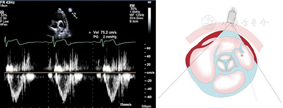

图5

胸骨旁主动脉瓣短轴切面,显示收缩期肺动脉峰值速度测量方法。在肺动脉瓣瓣上远心端1 cm处管腔中央获取